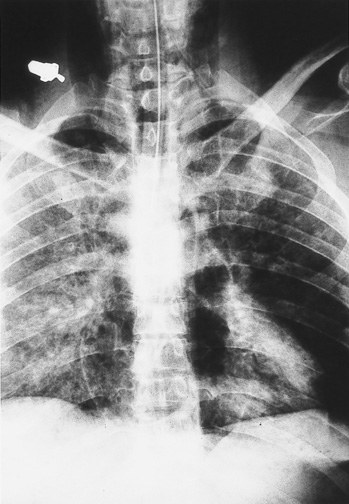

Erect postmortem x-rays and autopsy of the body performed 24 hours

after death revealed large amounts of gas in the venous system of the

trunk and limbs and in both sides of the heart (Figure 1). The heart

weighed 380 g and was normal, apart from foamy blood and gas in all

chambers. Analysis of gas from the right ventricle showed O 2

(20.6% by volume), and N 2 (75.9%). There was

bruising of the tongue and petechiae on the lungs and heart. The brain

(1740 g) showed mild cerebral oedema and a microscopic perivascular

haemorrhage in the floor of the fourth ventricle.

Figure 1: Postmortem erect chest x-ray, showing gas in both sides of the chest and in the neck veins (a combination of postmortem decompression, perimortem barotrauma and, possibly, decomposition).

Cerebral gas embolism and decompression illness were unlikely causes of death, as the subject was unresponsive before ascent. The gas observed at autopsy probably resulted from a combination of postmortem decompression (release of tissue nitrogen), perimortem barotrauma and, possibly, a degree of decomposition. 6